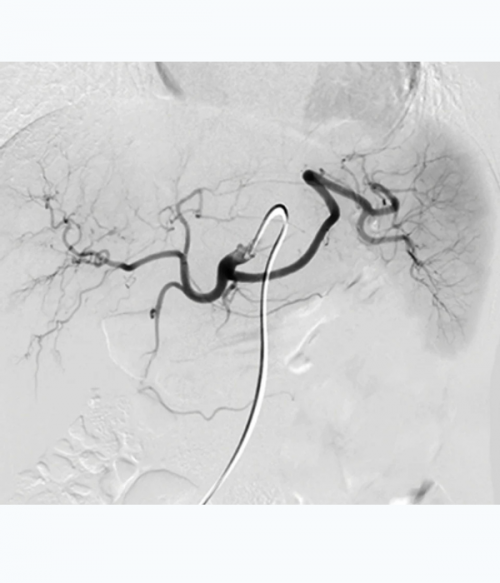

- Features 2,500+ high-quality print images (with an additional 800+ images in the complimentary eBook), including radiology images, full-color medical illustrations, clinical photographs, and gross pathology and histology images, and includes all relevant modalities: Ultrasound (with 3D), sonohysterography, hysterosalpingography, MR, PET/CT, and gross pathology imagery